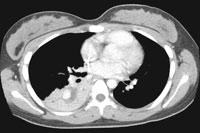

A repeat CT scan is seen below.

ENLARGE

this CT image.

WHAT

IS YOUR INTERPRETATION?